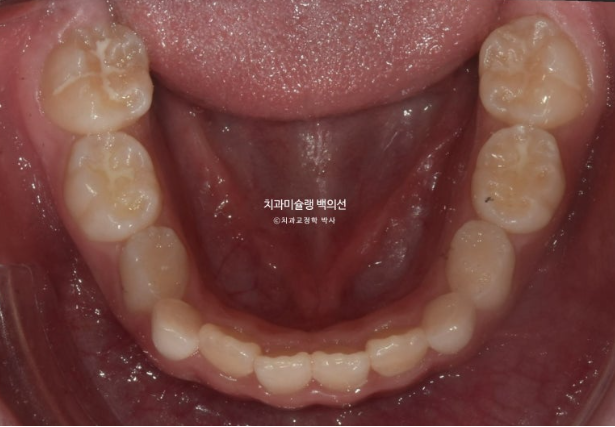

2022년 8월 내원한 어린이 입니다.

앞니 반대교합과 비대칭 치료를 위해 오셨습니다.

앞니 뿐 아니라 송곳니, 일부 어금니까지 거꾸로 물리는 상황입니다.

앞니 반대교합은 프리올소와 같은 장치로 간단하게 넘겨줄 수 있지만 더 큰 문제는 비대칭입니다.

아래앞니와 함께 아래턱이 우측으로 돌아가 있습니다.